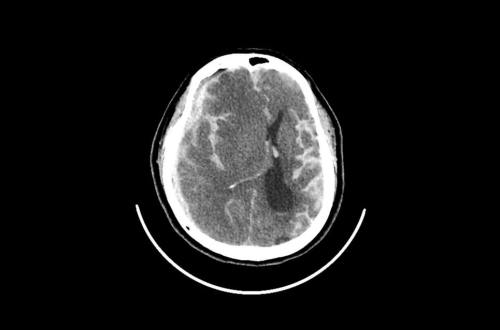

For its relatively small size, the brain consumes a ridiculous amount of power: 20 to 30 percent of the body’s energy at rest. To fuel all of its neurons, the brain depends on oxygen. When someone has a stroke or a head injury, the flow of oxygenated blood to the brain gets disrupted. Starved of oxygen, the brain tissue is damaged, leading to a host of problems with memory, speech, strength, and motor control.